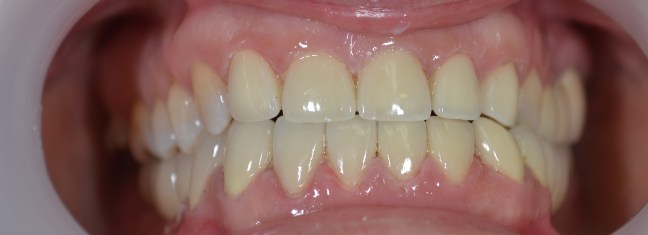

Kozmetikai és funkcionális kezelés: felső torlódott fogak kiegyenesítése, koronák enyhe kifele döntése, mélyharapás korrigálása.

A választott korona típusa: CAD/CAM (komputer vezérelt tervezés/megmunkálás) technológiával készült cirkónium (fémmentes) szóló koronák.

A választott fogszín: A2

A protetikai munka elkészülésének ideje: 5 munkanap.